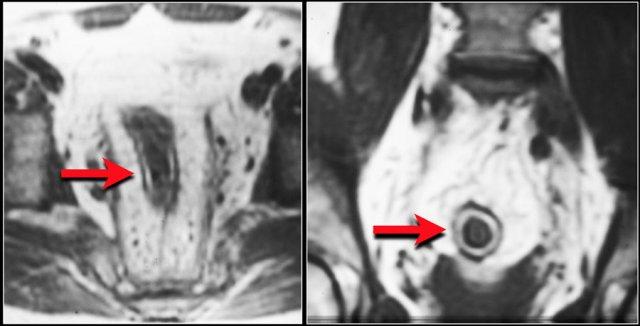

Bệnh Crohn mạn tính

Đây là hình ảnh của một bệnh nhân mắc bệnh Crohn mạn tính có hình thành sẹo co rút (cicatrization).

Ở những bệnh nhân này, thành ruột cứng như đá và sẽ không đáp ứng với corticosteroid hay các thuốc điều trị khác.

Thiếu máu cục bộ mạc treo ruột

Thiếu máu cục bộ ruột thường ảnh hưởng đến đại tràng và hay gặp nhất ở góc lách, đại tràng xuống và đại tràng sigma.

Nguyên nhân chủ yếu là do tình trạng giảm lưu lượng máu như sốc giảm thể tích hoặc suy tim sung huyết.

Đặc biệt ở người cao tuổi có dày thành ruột, cần luôn đưa thiếu máu cục bộ vào danh sách chẩn đoán phân biệt.

Đây là hình ảnh bệnh nhân thiếu máu cục bộ ruột do huyết khối tĩnh mạch mạc treo tràng trên – SMV (mũi tên đỏ).

Lưu ý tình trạng ứ máu tĩnh mạch trong mạc treo ruột (mũi tên vàng).

Đây là một bệnh nhân khác bị thiếu máu cục bộ một đoạn dài ruột non do tắc ruột quai kín.

Một đặc điểm hình ảnh quan trọng của tắc ruột quai kín là hình ảnh các quai ruột non giãn xếp theo kiểu nan hoa bánh xe với các mạch máu mạc treo hội tụ về một điểm trung tâm.

Các dấu hiệu thiếu máu cục bộ trong tắc ruột quai kín tương tự như ở các bệnh nhân có nguyên nhân thiếu máu cục bộ mạc treo khác:

- Dày thành ruột

- Phù nề mạc treo ruột

- Cổ trướng

- Sự ngấm thuốc của thành ruột trong thiếu máu cục bộ có thể bình thường, tăng do hiện tượng tái tưới máu, hoặc giảm/mất ngấm thuốc như trong trường hợp này.